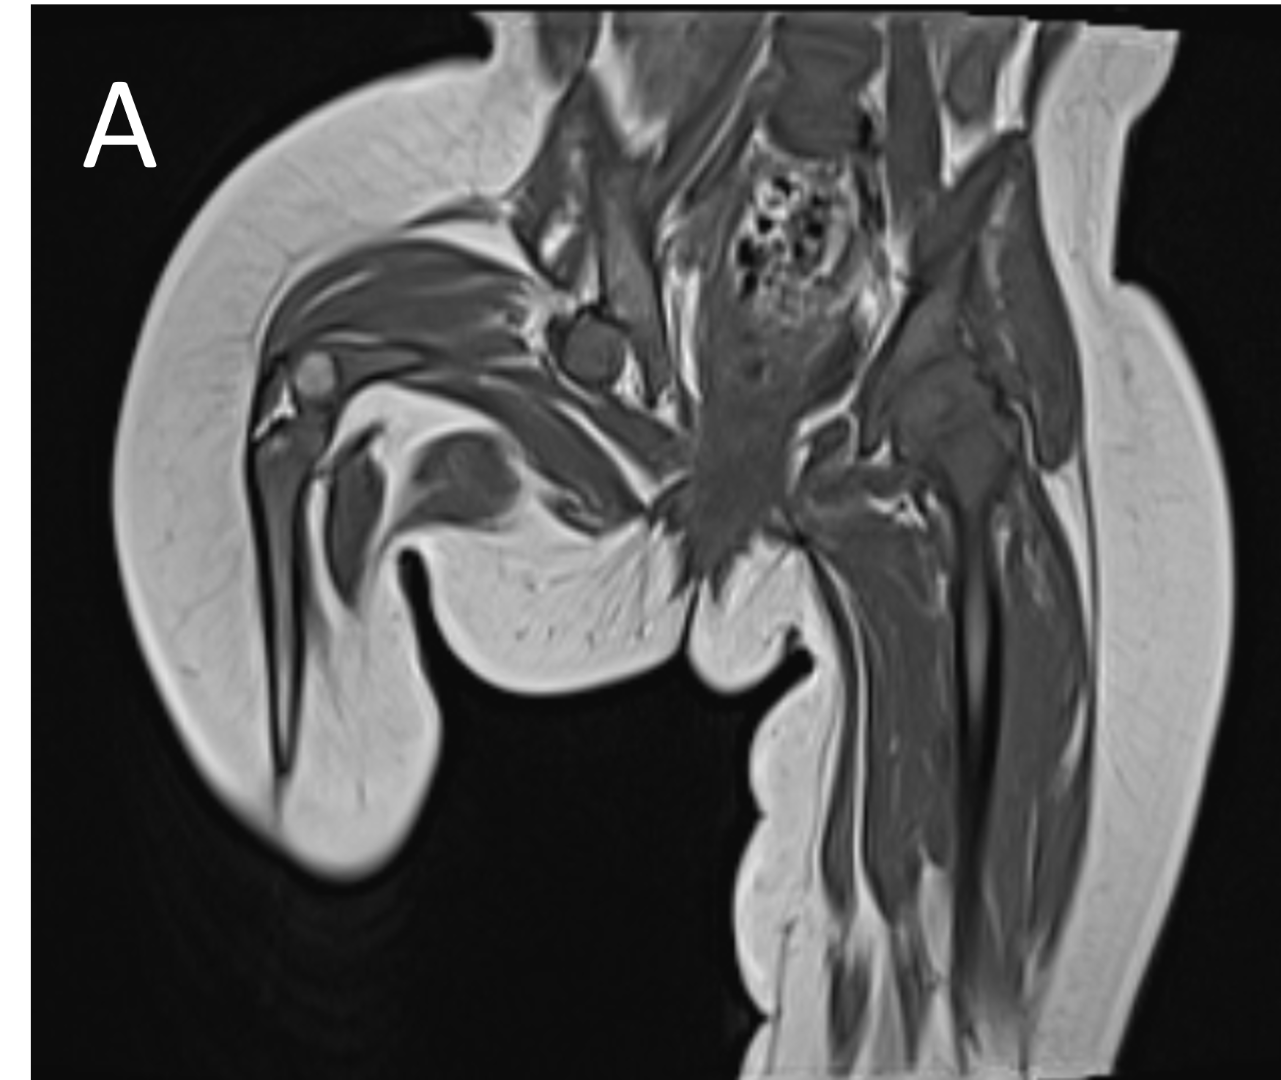

- A.FINDINGS – MR BILATERAL HIPS

- A.LEGENDS – MR BILATERAL HIPS :Right femur is shortened, with a coxa vara deformity. Femoral shaft measures 7.2 cm in length. The acetabulum is moderately dysplastic and anteriorly rotated, But contains the femoral head. The femoral head and neck appear hypoplastic and posteriorly and externally rotated.